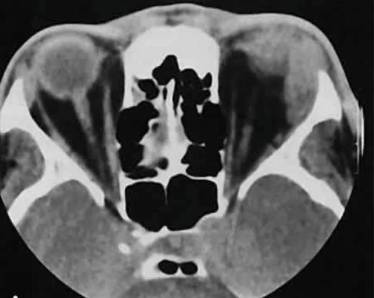

Диагностика включает:

- лабораторные исследования крови и тканей из ран;

- рентген позвоночника;

- МРТ;

- КТ.